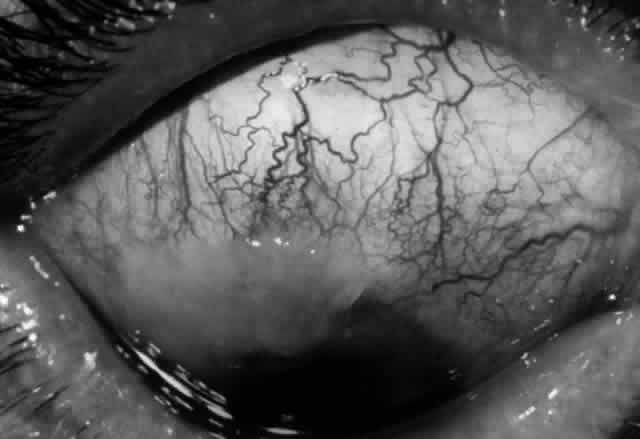

Ocular complications in pemphigus are rare,5 but ocular manifestations of pemphigus on lids, conjunctiva, cornea, lens, and iris have been reported. Conjunctival bullae are infrequently seen in pemphigus vulgaris. More typically, a catarrhal or purulent conjunctivitis develops.3 The ocular features are similar in pemphigus foliaceus and are usually confined to the palpebral conjunctiva, with erythema, edema, and purulent discharge.5,12 Pemphigus foliaceus may also produce entropion and trichiasis of both lids with resultant corneal damage. Lens opacities have been described in 5% of patients with a form of pemphigus foliaceus that is endemic to Brazil. Some of these patients also exhibit red, nodular iris lesions, the exact nature of which is not known.12

The conjunctival involvement in pemphigus may lead to symblepharon as a result of the formation and rupture of small vesicles. This does not, however, lead to progressive scarring and blindness, as is so often the case in cicatricial pemphigoid (Fig. 4).13